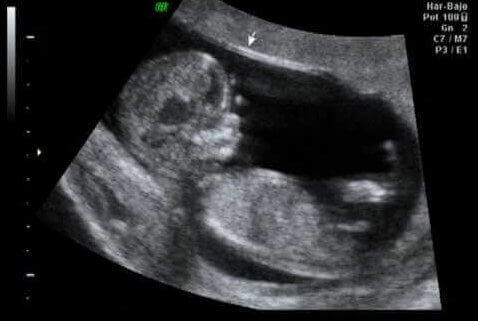

Échographie à la douzième semaine de la grossesse

Point culminant du premier trimestre, la douzième semaine est généralement le point idéal pour effectuer un contrôle sur ce tiers de la grossesse : la première échographie. Il est ainsi vérifié que les organes se développent correctement.

On vérifie également la taille et le poids du bébé, ainsi que la présence de la translucidité nucale, le liquide que tous les fœtus ont dans le cou.

Il s’agit d’un moment très important, car les spécialistes affirment qu’entre 60% et 70% des problèmes de malformation que le fœtus peut présenter peuvent être détectés à ce stade.

D’autre part, l’épaisseur de la nuque du fœtus se mesure et sa valeur fait partie du dépistage du premier trimestre. En effet cela permet de détecter le risque d’anomalie dans le nombre de chromosomes (connu sous le nom d’aneuploïdies), notamment la trisomie 21 ou le syndrome de Down.

Ceci est fait à partir du lien entre ces données et d’autres études incluant :

- Âge maternel

- Les valeurs hormonales.

- La valeur de la clarté nucale.

La première échographie permet de détecter entre 60% et 70% des problèmes de malformation du fœtus.

La partie excitante de l’échographie, en plus de percevoir la première activité du fœtus, est l’estimation de la date prévue pour l’accouchement. Quoi qu’il en soit, et sans aucune intention de vous décevoir, cela n’est vrai que 5% du temps.